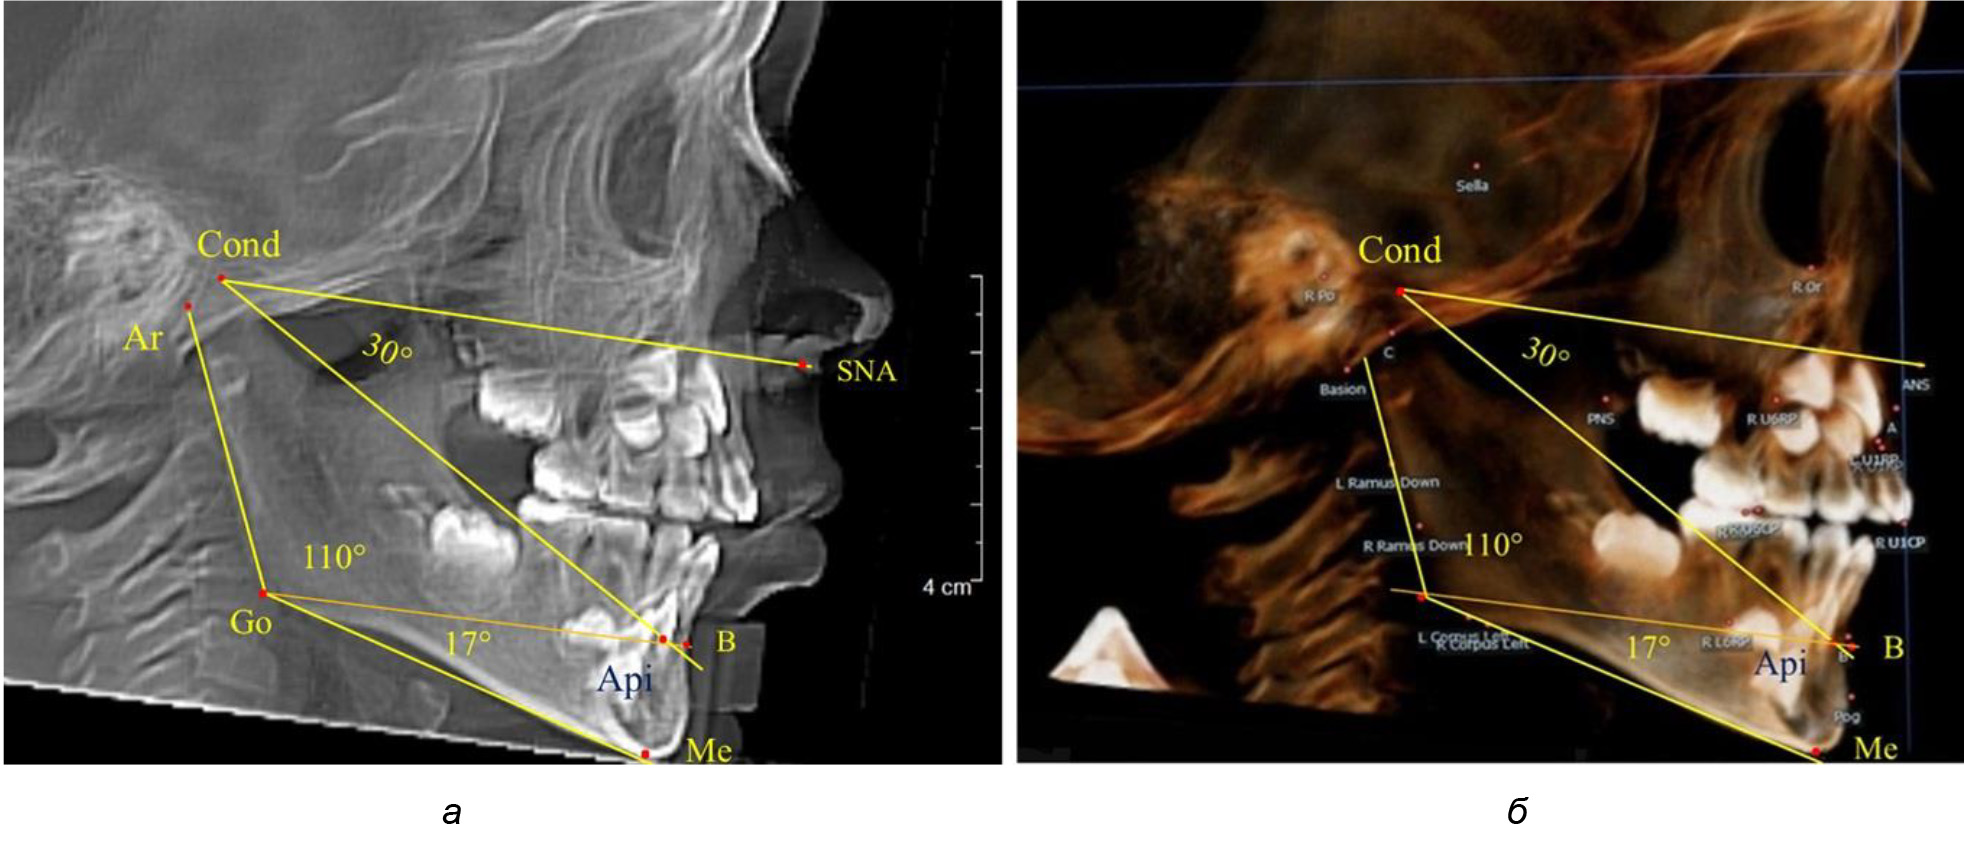

При анализе ТРГ 5 детей в периоде прикуса молочных зубов отмечено, что величина основного угла гнатической части лица SNA-Cond-Api, как правило, в норме составляла около 30°, и его величина была относительно стабильной у всех обследованных детей. В то же время угол нижней челюсти и его составляющие отличались вариабельностью параметров при различных показателях нижнечелюстного угла (рис. 4).

Рис. 4. Особенности ТРГ (а) и 3D-модели (б) в периоде прикуса молочных зубов

Таким образом, в периоде молочного прикуса с оптимальными окклюзионными соотношениями, несмотря на линейные размеры в вертикальном и сагиттальном направлении, которые, безусловно, меньше параметров взрослых людей, величина основного угла гнатической части лица SNA-Cond-Api соответствовала параметрам людей с полностью сформированным физиологическим прикусом постоянных зубов. Анализируя данные рентгенограмм детей в периоде сменного прикуса, отмечено, что величина основного угла гнатической части лица SNA-Cond-Api, так же как в молочном и постоянном прикусе, в норме составляла от 28 до 32°. В то же время угол нижней челюсти и его составляющие отличались вариабельностью параметров при различных показателях нижнечелюстного угла. Достоверных различий угла гнатической части после смены нижних медиальных резцов и прорезывания первых постоянных моляров (4 ребенка) не было; происходил очередной этап подъема высоты прикуса и увеличение линейных размеров костей гнатической части, однако угловые параметры были относительно стабильны. После смены всех резцов и замены первых молочных моляров первыми премолярами (6 человек) увеличивались линейные размеры при сохранившихся угловых показателях гнатической части лица (рис. 5).

После смены всех молочных зубов (анализ 9 ТРГ) и после прорезывания вторых постоянных моляров (7 человек) происходил очередной этап подъема высоты прикуса с увеличением размеров костей гнатической части лица. Однако величина основного угла гнатической части лица SNA-Cond-Api, так же как в молочном и сменном прикусе, в норме составляла (30,02 ± 1,25)°, что не имело достоверных различий (р ˃ 0,05) с аналогичным параметром, анализируемом в других группах исследования. Угол нижней челюсти и его составляющие отличались вариабельностью параметров при различных показателях нижнечелюстного угла (рис. 6).

Рис. 6. Варианты 3D рентгенограмм детей после смены всех молочных зубов (а) и после прорезывания вторых моляров (б)